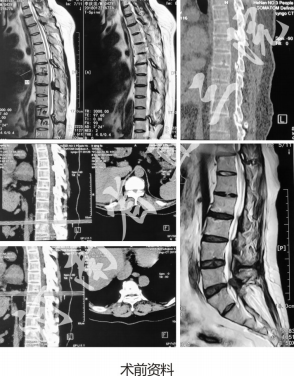

患者:李××,男

主诉:腹部及双下肢感觉减退伴下肢无力5月,加重20天

既往史:脑梗后遗症、高血压、糖尿病

查体:左侧直腿抬高试验70°,加强试验阴性。右侧直腿抬高试验70°,加强试验阴性。双侧大腿滚动试验阴性,平剑突下10cm以下感觉减退,左侧重于右侧,双下肢肌力下降,左上肢肌力下降

诊断:双下肢不全瘫、胸椎T6/7、T8/9、T10/11椎管狭窄、腰5/骶1椎管狭窄手术:分次进行导航引导下胸6/7、胸8/9、胸10/11后路内窥镜椎管扩大减压术、导航下Delta引导下L5/S1椎间盘摘除术